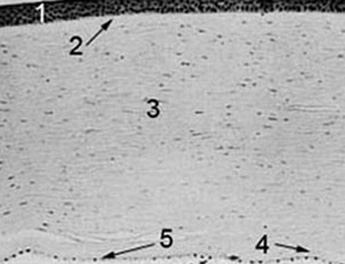

Corte Histopatológico de la Córnea

La córnea está formada por 5 capas: El Epitelio (1), la capa de Bowman (2), el Estroma (3), la membrana de Descemet (4) y el Endotelio (5).